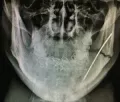

Первые дни только привыкал к шинам, но быстро адаптировался, так как не впервой. От госпитализации я отказался, решил, что в домашних условиях справлюсь. Сделал контрольный снимок, проконсультировался с хирургом-стоматологом и он, посмотрев на снимок и на шины, сказал, что процесс заживления идёт нормально.

Снимок прилагаю (был сделан на 5-й день после шинирования).

Теоретически все нормально, но справа имеется серьёзный костный дефект с повреждением нижнечелюстного канала. Рекомендую Вам обратиться к лечащему врачу.